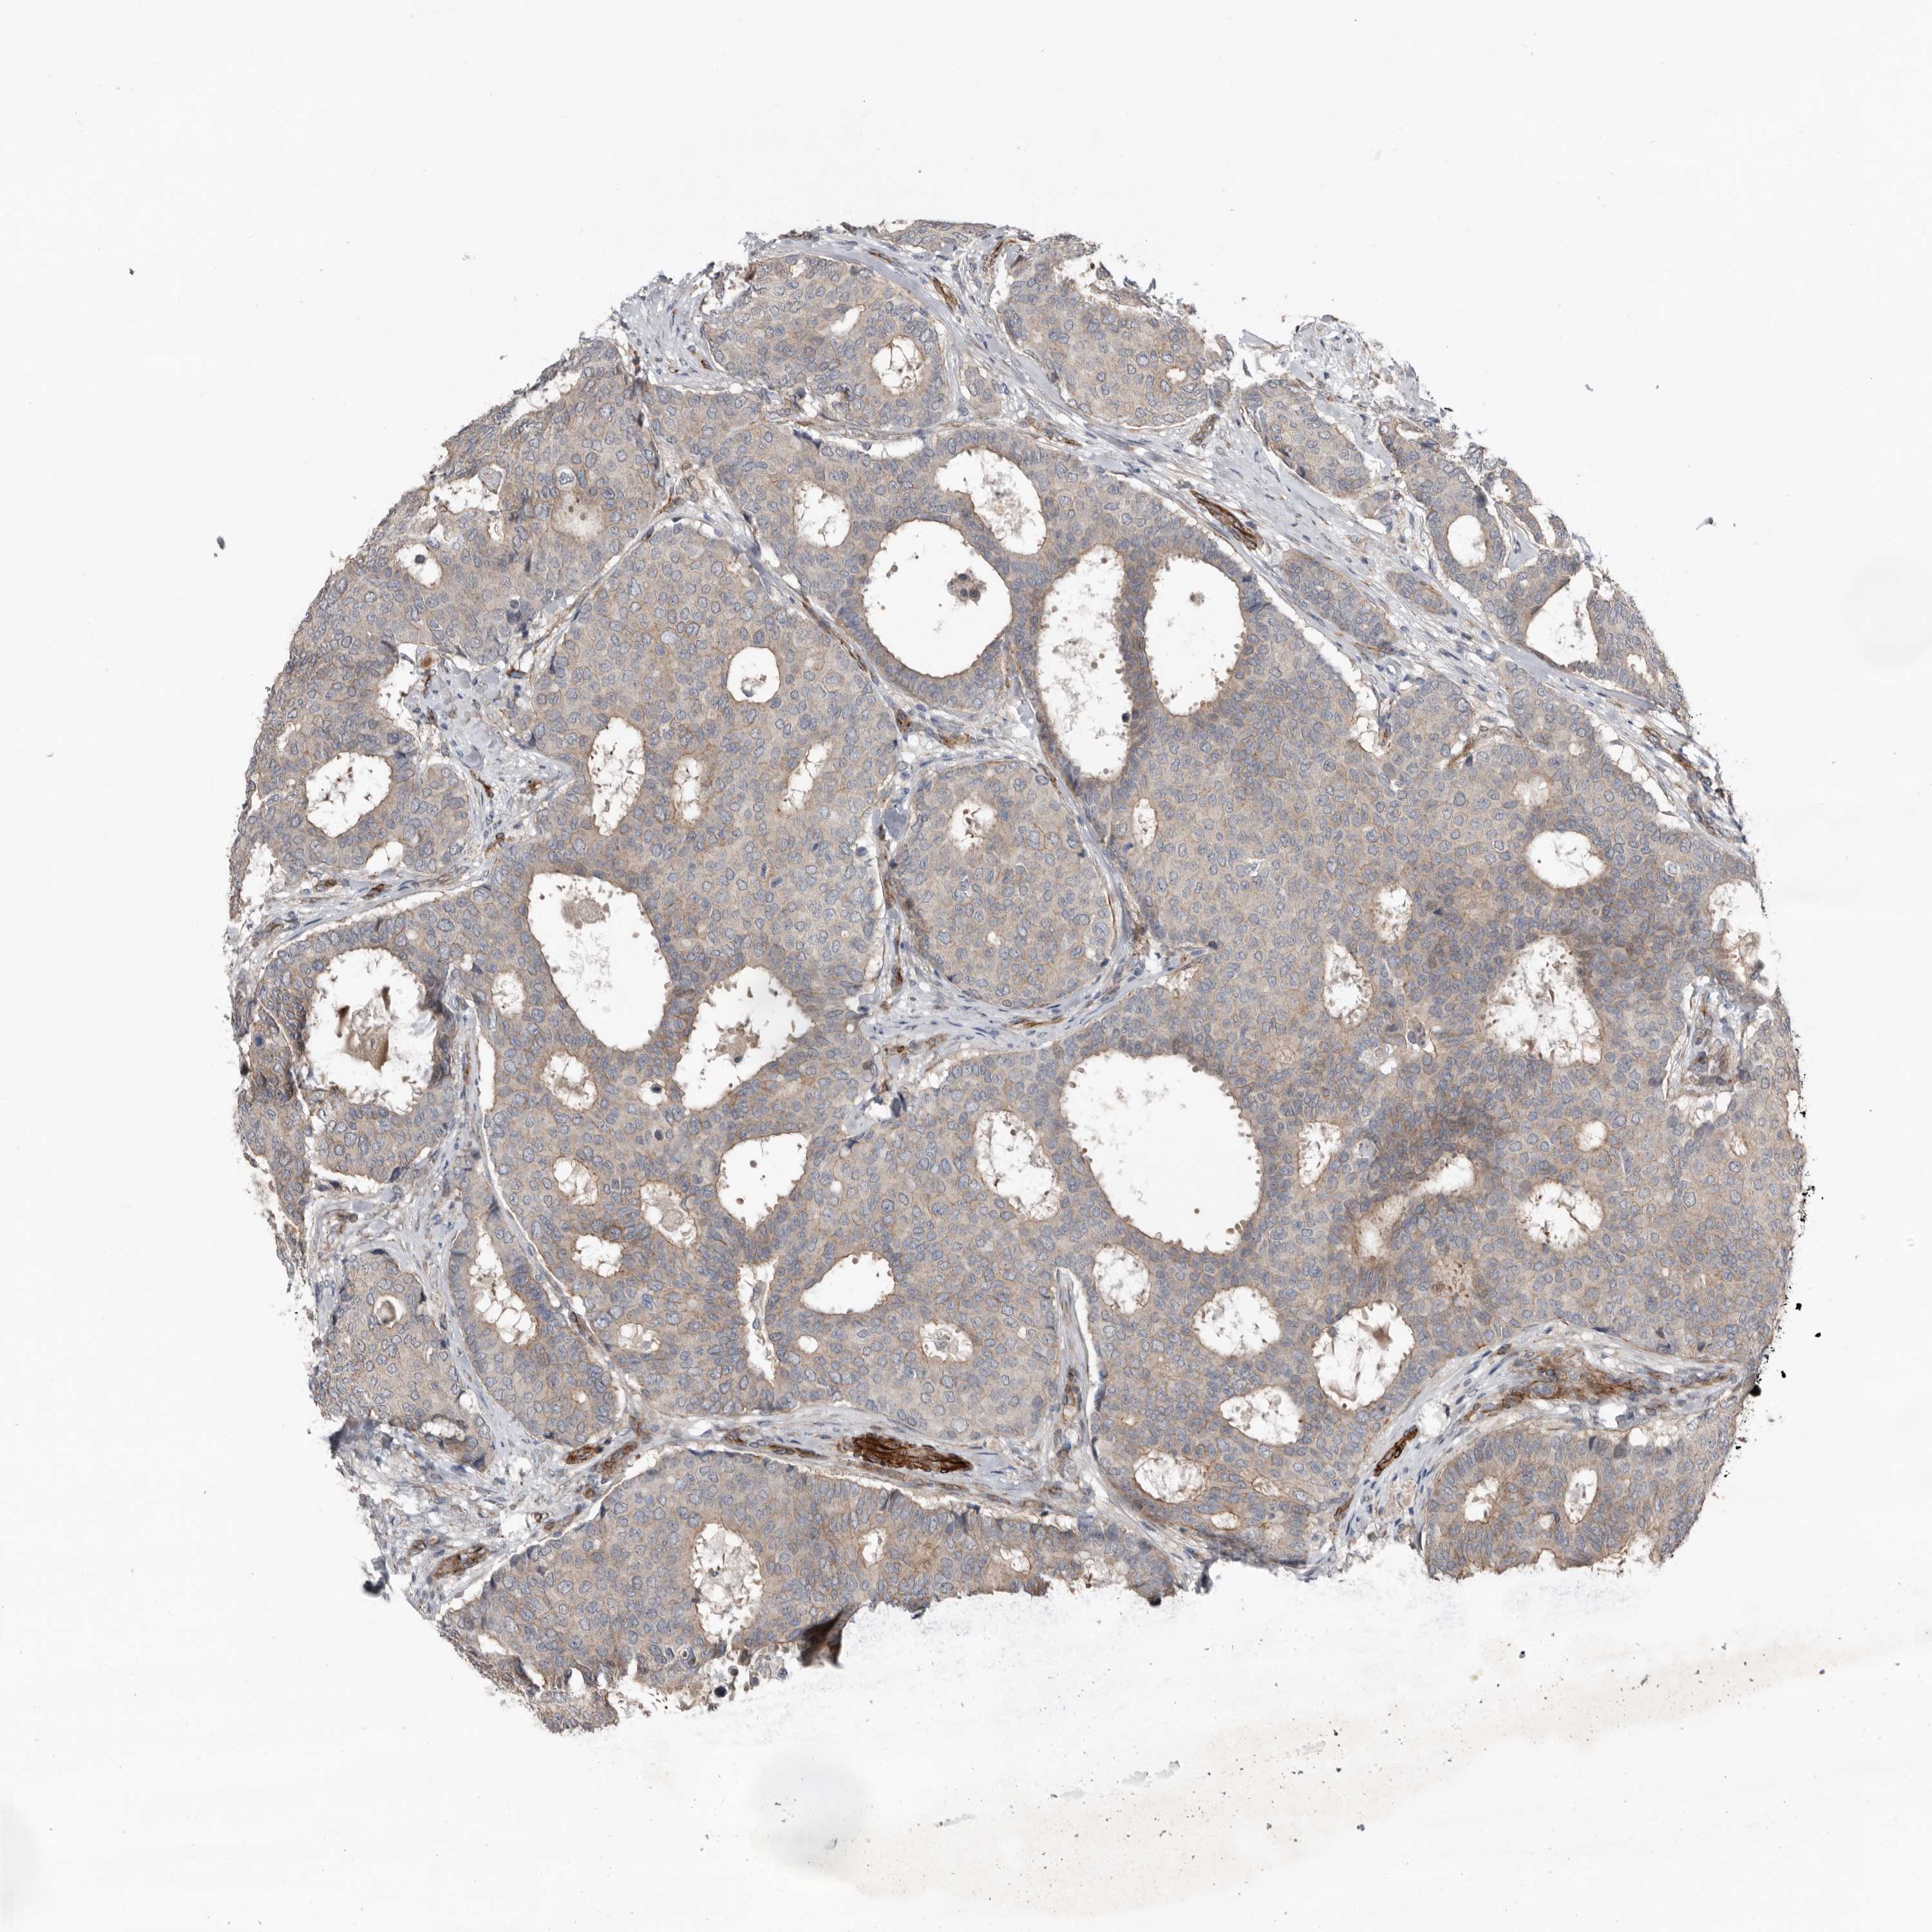

CANCER BREAST CANCER Show tissue menu

BRCA TCGA BRCA VALIDATION PROTEIN EXPRESSION

ANTIBODIES

AND

VALIDATION

RANBP17 is not prognostic in Breast Invasive Carcinoma (TCGA)